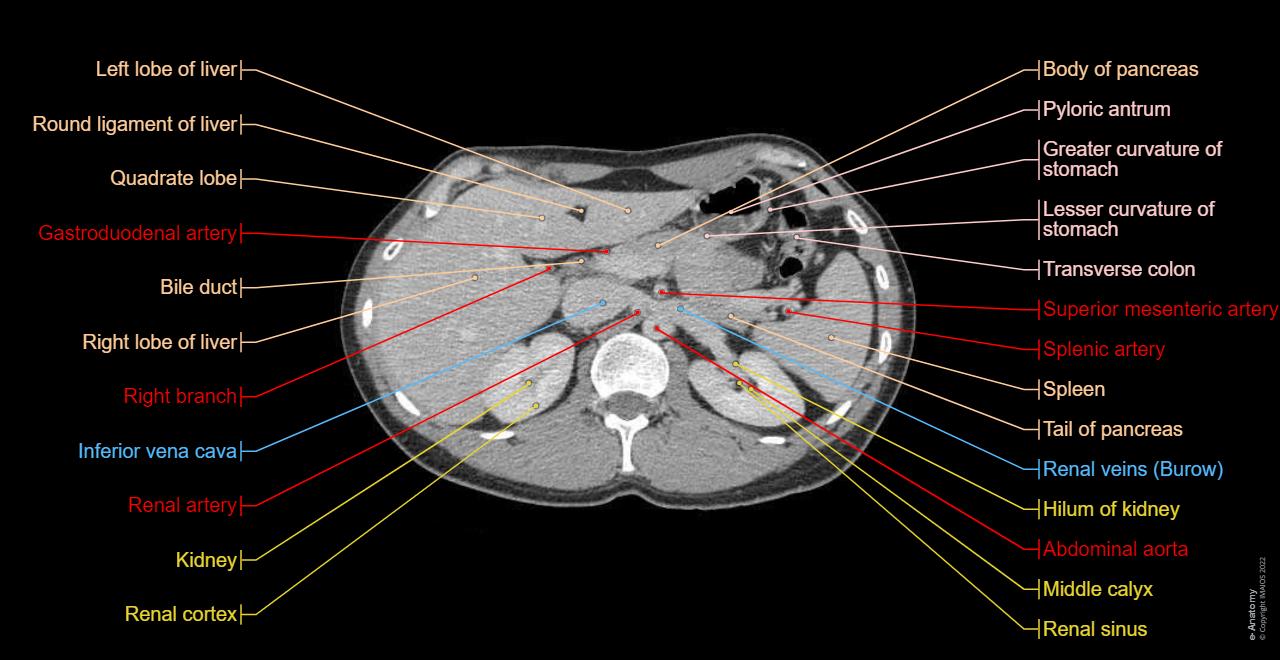

- 영상은 장기 구조, 밀도 변화, 병변의 크기와 형태, 주변 조직과의 경계 등을 보여 줍니다.

- 복부 CT는 복부와 골반을 포함한 넓은 범위를 한 번에 관찰할 수 있어, 내부 장기뿐 아니라 복막, 혈관계, 림프계 병변 탐색에도 유용합니다.

신장 / 비뇨계 질환

- 신장 결석 (신요관 결석)

비조영(non-contrast) CT는 신결석 탐지에 특히 민감하며, 결석의 크기·밀도·위치를 파악할 수 있습니다 . - 수신증 / 요관 폐색

복수의 낭종 구조를 CT에서 쉽게 분리해 볼 수 있습니다. - 신장 혈관 문제 (renal artery stenosis, thrombosis 등)

혈관 조영 CT 또는 동맥기·정맥기 영상에서 혈관 협착, 폐색 유무를 평가할 수 있습니다 .

복부 혈관계 및 기타

- 복부 대동맥류 (Abdominal aortic aneurysm, AAA)

대동맥의 직경 확대, 파열 위험성을 CT에서 측정하고 확인할 수 있습니다 . - 혈관 폐색, 동맥 박리